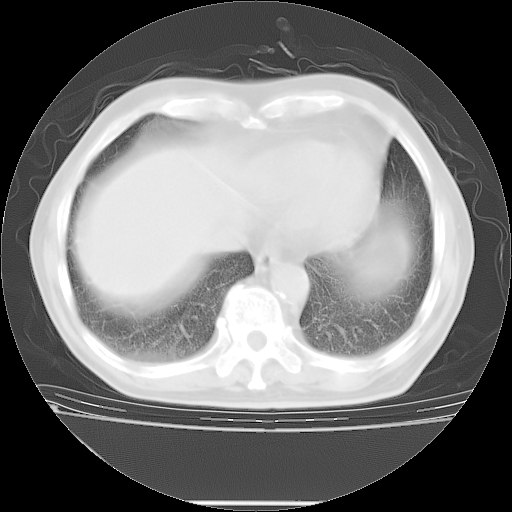

今天复查肺部CT,发现双肺广泛磨玻璃样改变。所以我把3月19日和5月9日相隔50天的肺部CT上传。请大家会诊。

5月9日肺部CT(在4月27日齐鲁医院肺部CT描述部分肺组织磨玻璃样改变,12天后肺组织广泛磨玻璃样改变)

2009年5月9日肺部CT

大致读了系列胸部CT:纵隔窗无明显异常,肺窗:从4、27至今:主要是双肺中下野外带可见毛玻璃样改变,目前处于急性肺泡炎阶段,至于原因考虑1、结替组织或胶原血管性疾病所致?2、恶性疾病如恶组在肺部所致的表现或细支气管肺泡癌?3、药物或其它原因如肺蛋白沉着症所致肺泡炎目前不太可能?总之,明天就去请我院的呼吸科、感染科、血液科和临免专家会诊哈。